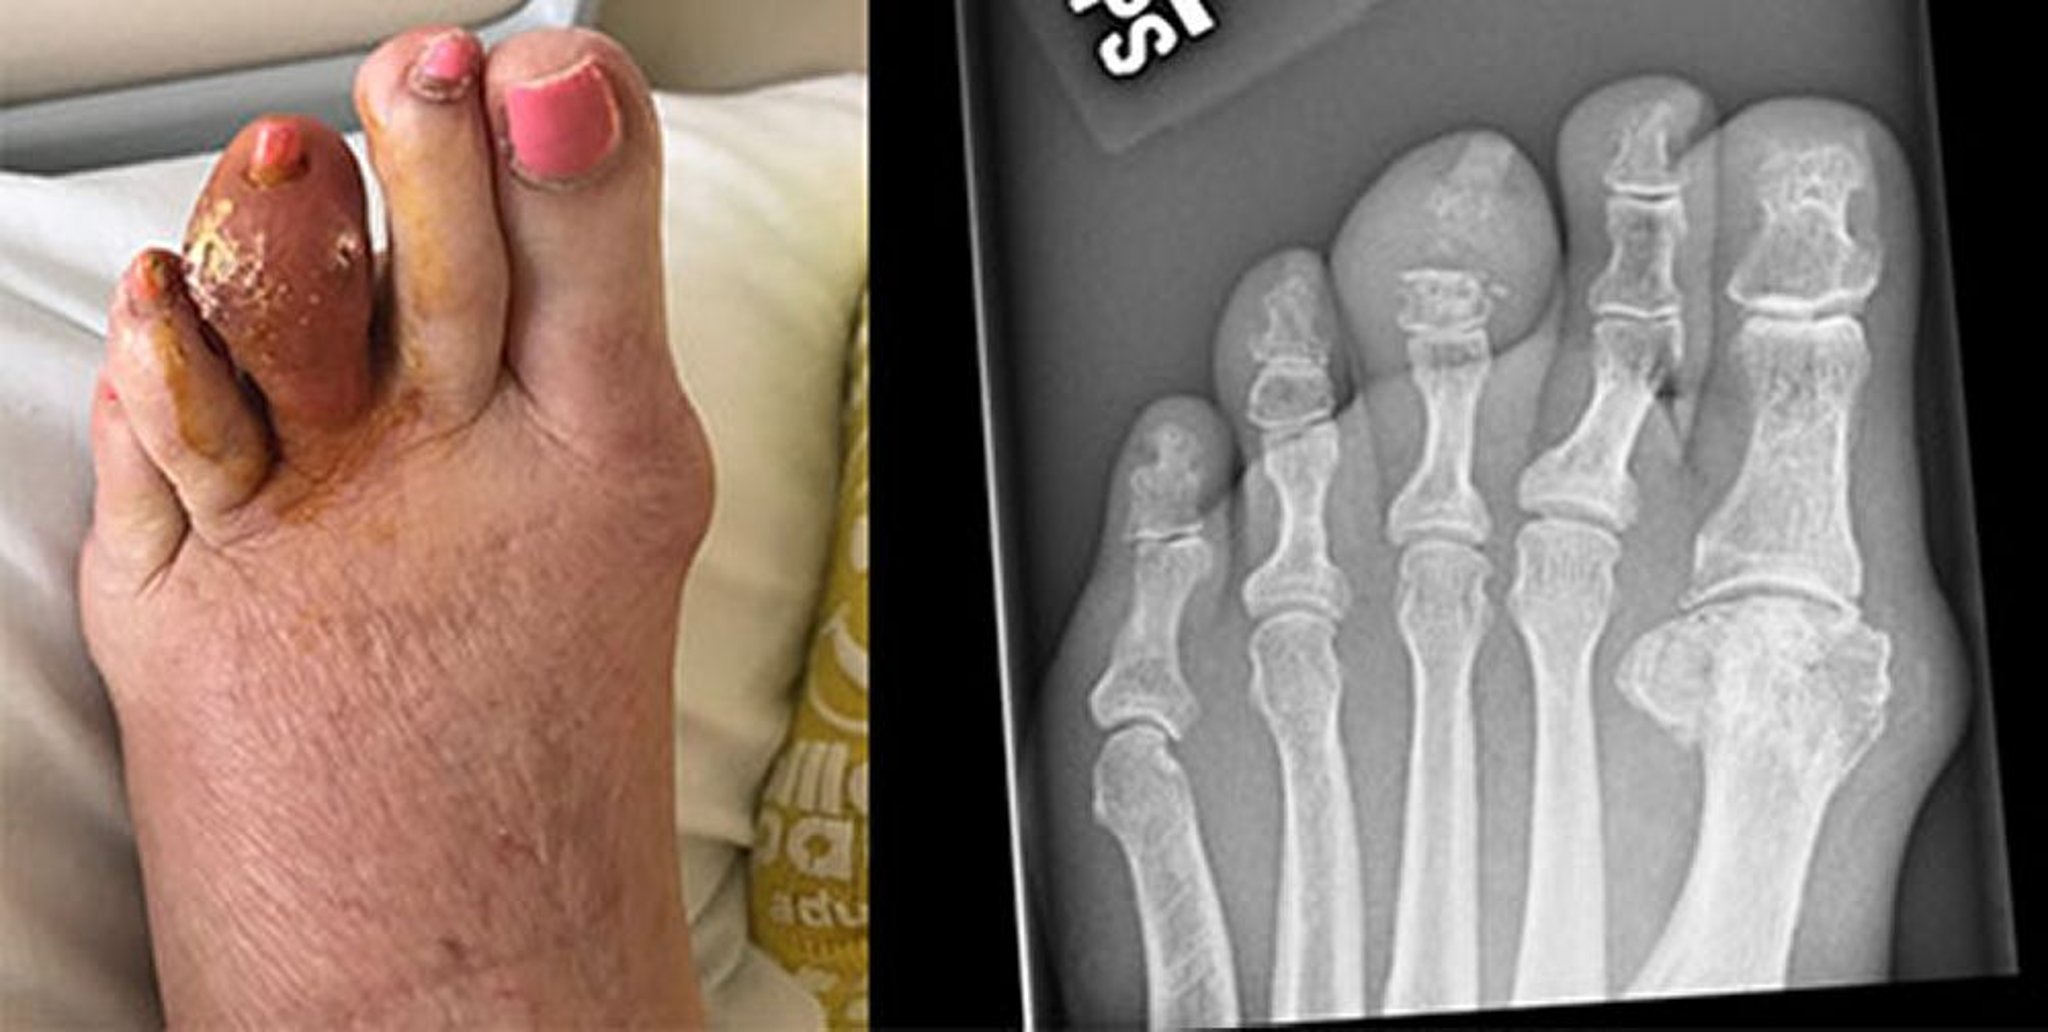

Gotta del dito medio

Questa foto mostra un grande tofo del terzo dito sinistro, che si è rotto e ha rilasciato acido urico indurito. La radiografia a destra mostra l'erosione della falange media e dell'articolazione interfalangea distale.